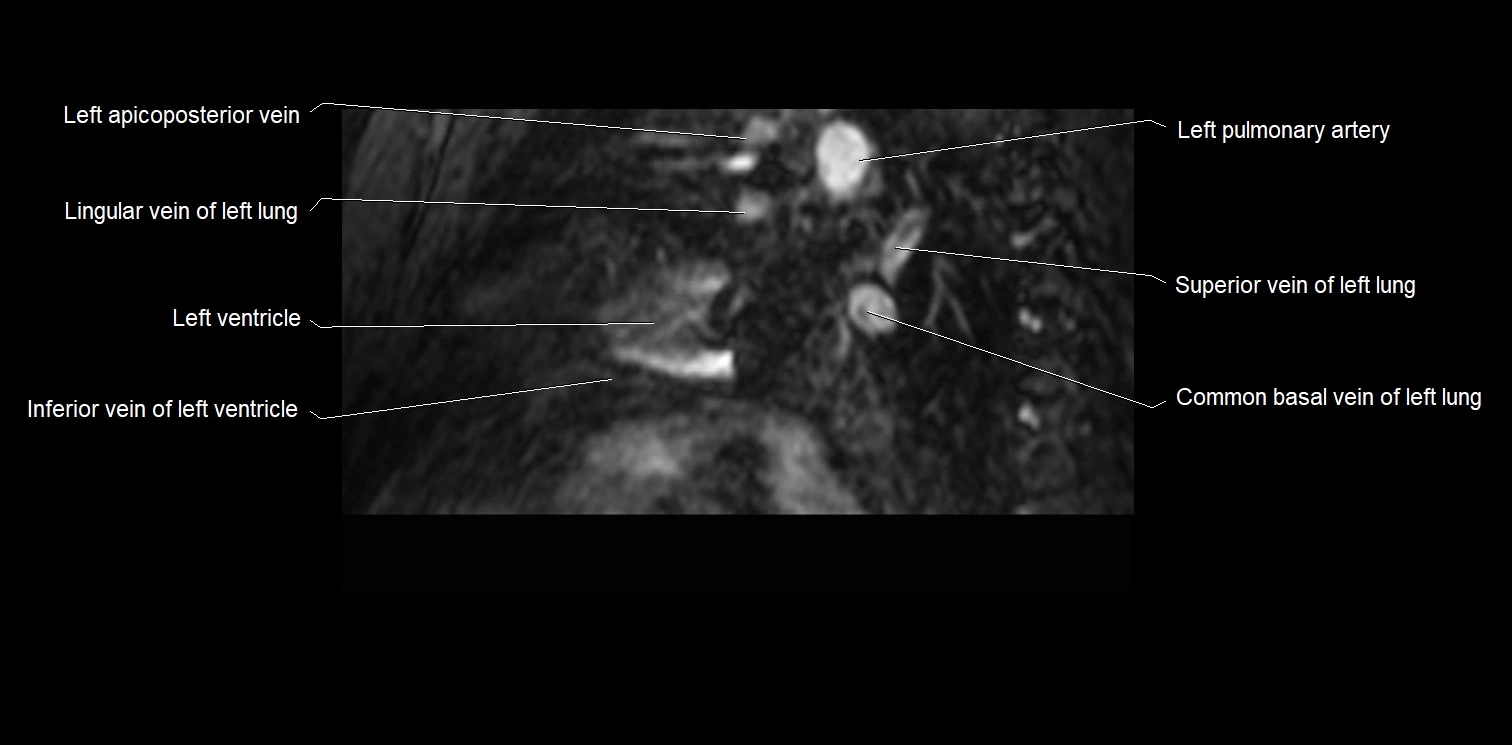

MRI image